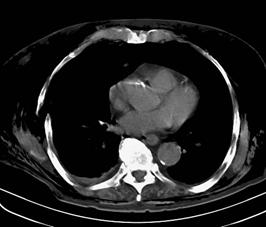

Pneumotorace sufocant bilateral Pneumotorace sufocant stang

Pneumotorace

sufocant stang Pneumotorace

sufocant drept Pneumotorace

sufocant drept

Imagine

CT Imagine CT